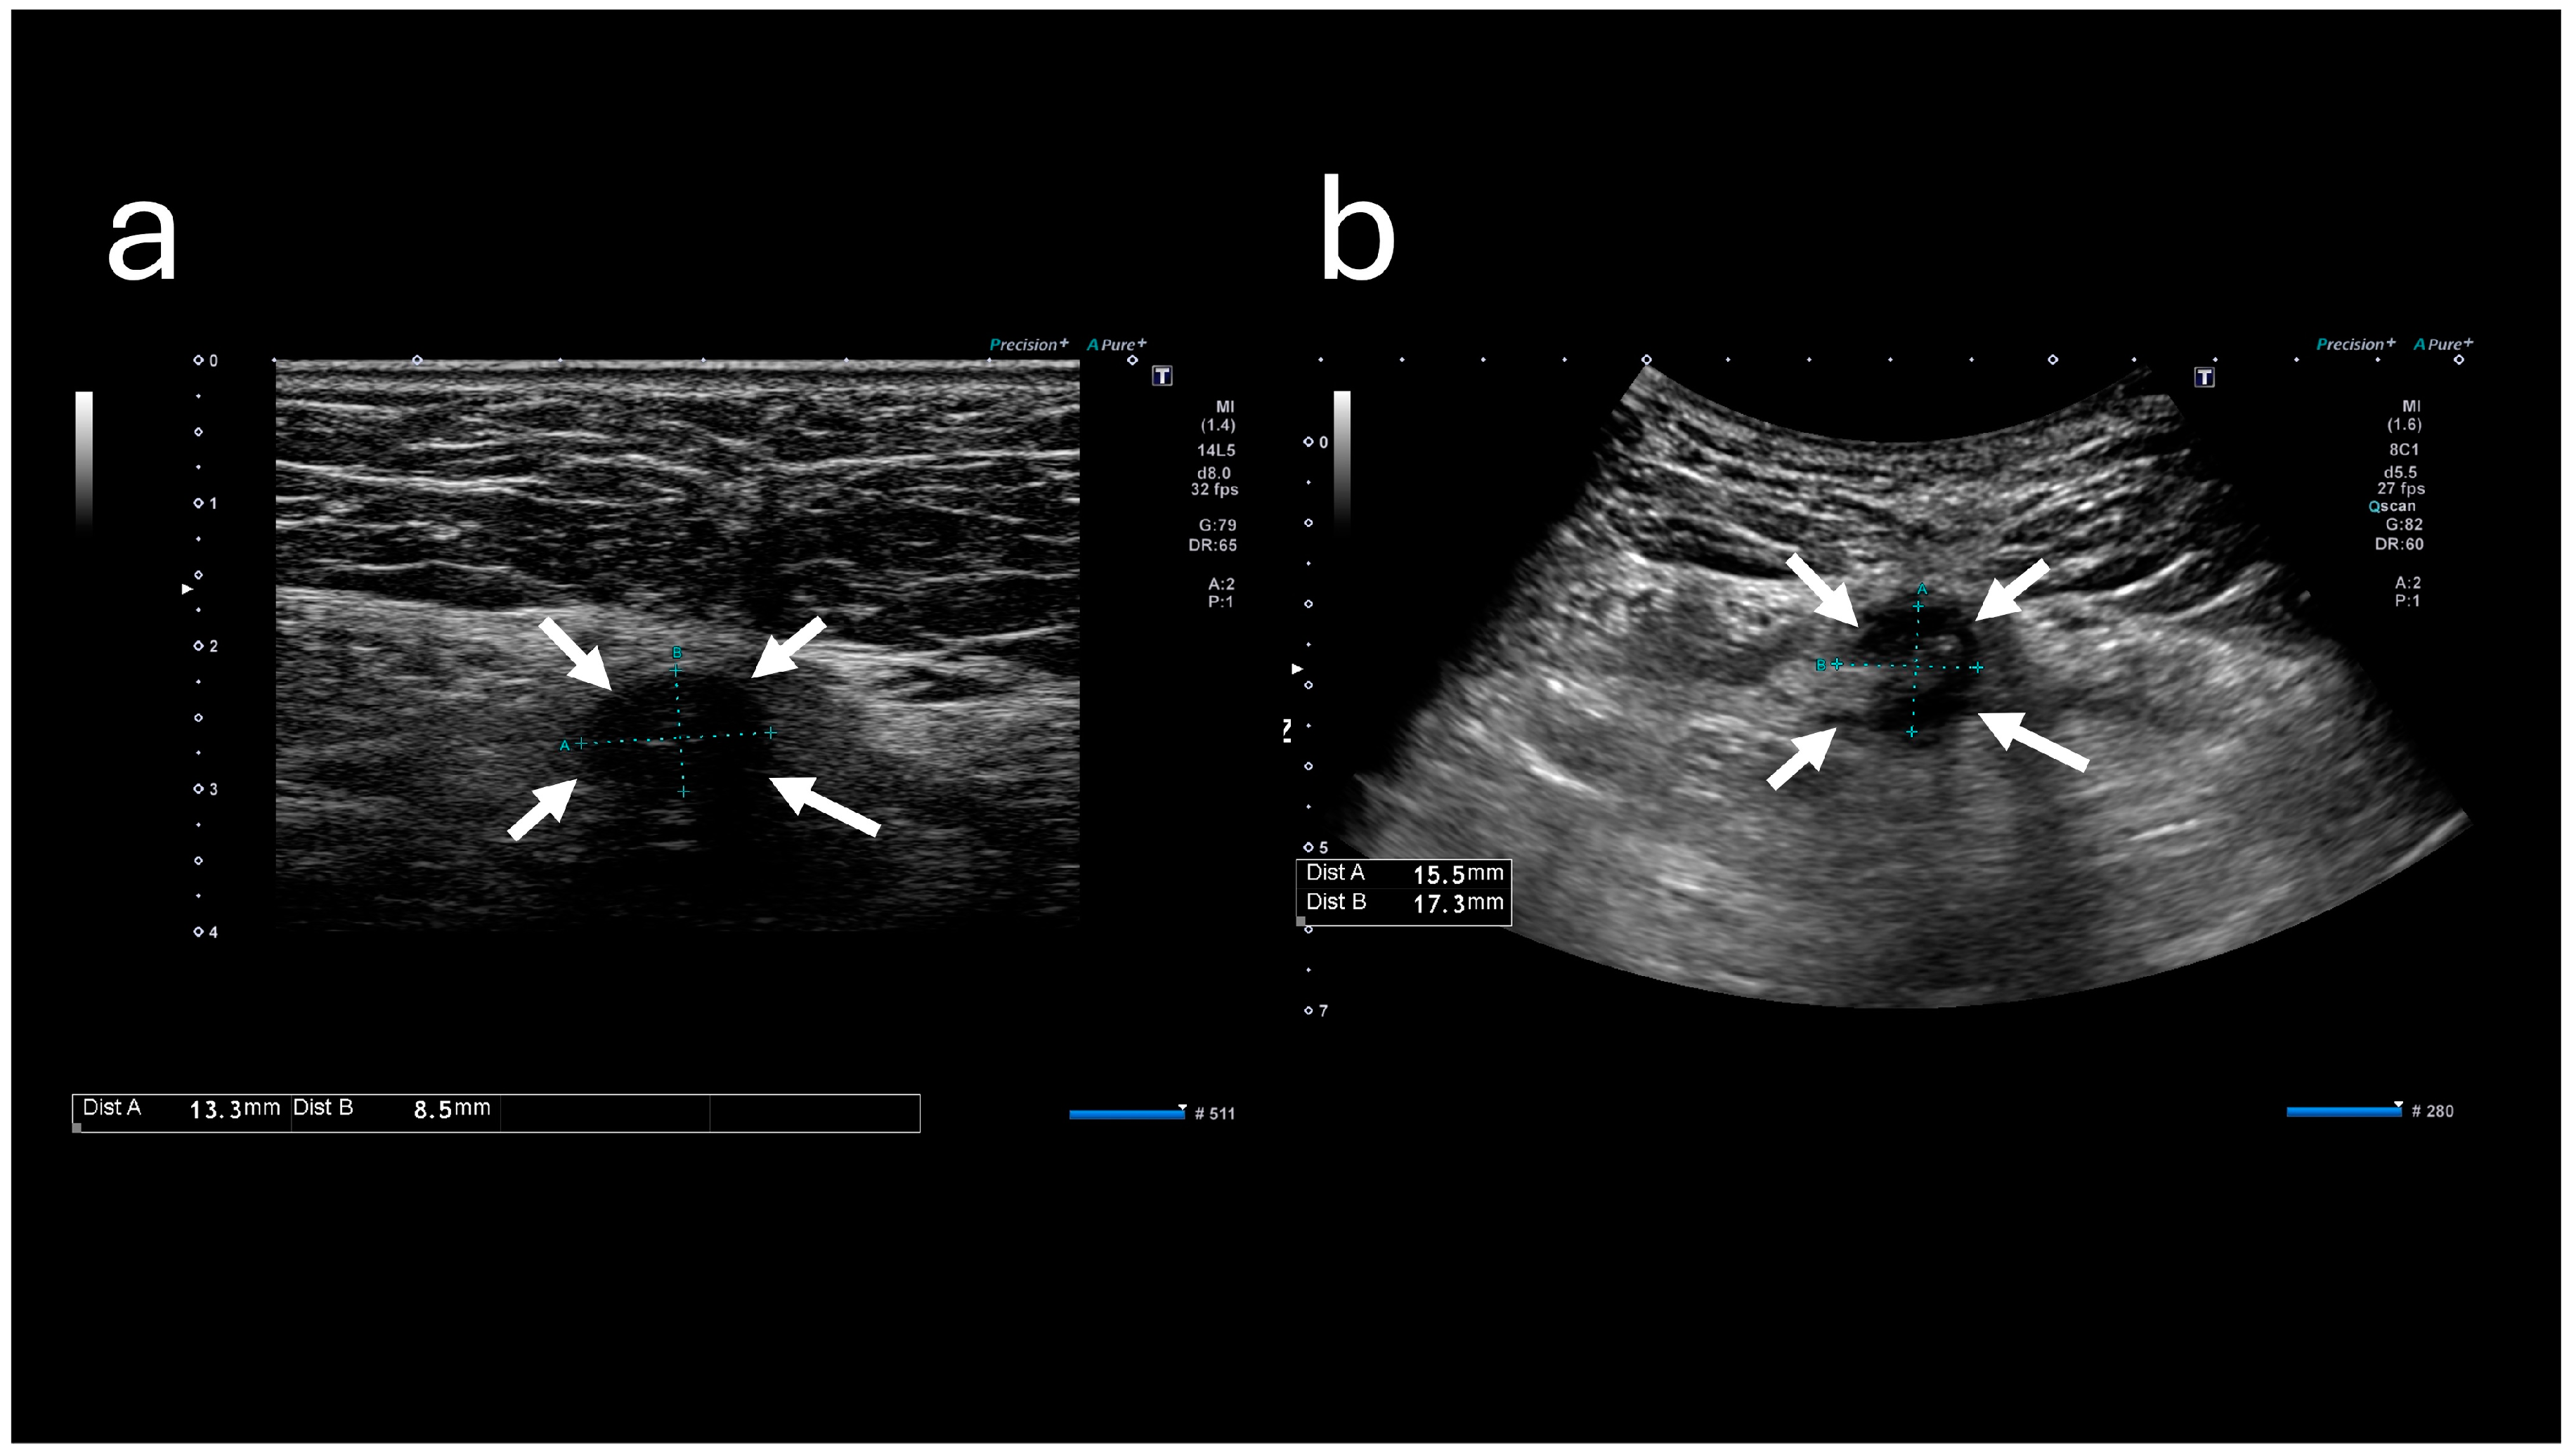

The A-US and A-CT findings suggested the enlargement of the abscess below the umbilicus. Enhanced A-CT revealed multilocular abscesses (Figure 4 and Figure 5). The abscess was drained with the patient under sedation, with local anesthesia administered as follows: intravenous midazolam (3 mg), intravenous pentazocine (15 mg), and subcutaneous injection of lidocaine (8 mg). When the base of the umbilicus was opened with mosquito forceps, a large amount of purulent discharge was observed (Figure 6). The umbilicus was carefully washed, and a drainage tube was inserted at its base. The Gram stain of the pus showed a multi-bacterial pattern including Gram-positive cocci, Gram-positive rods, and Gram-negative rods (Figure 7). He was hospitalized at our hospital, and the oral antibiotic was changed to intravenous ampicillin/sulbactam (3 g every 8 h).

Figure 4. Abdominal ultrasound sonography images. (a) Image obtained at the time of initial visit. (b) Image obtained at the time of the second visit. The low-echoic lesion (indicated by arrows) appears enlarged.